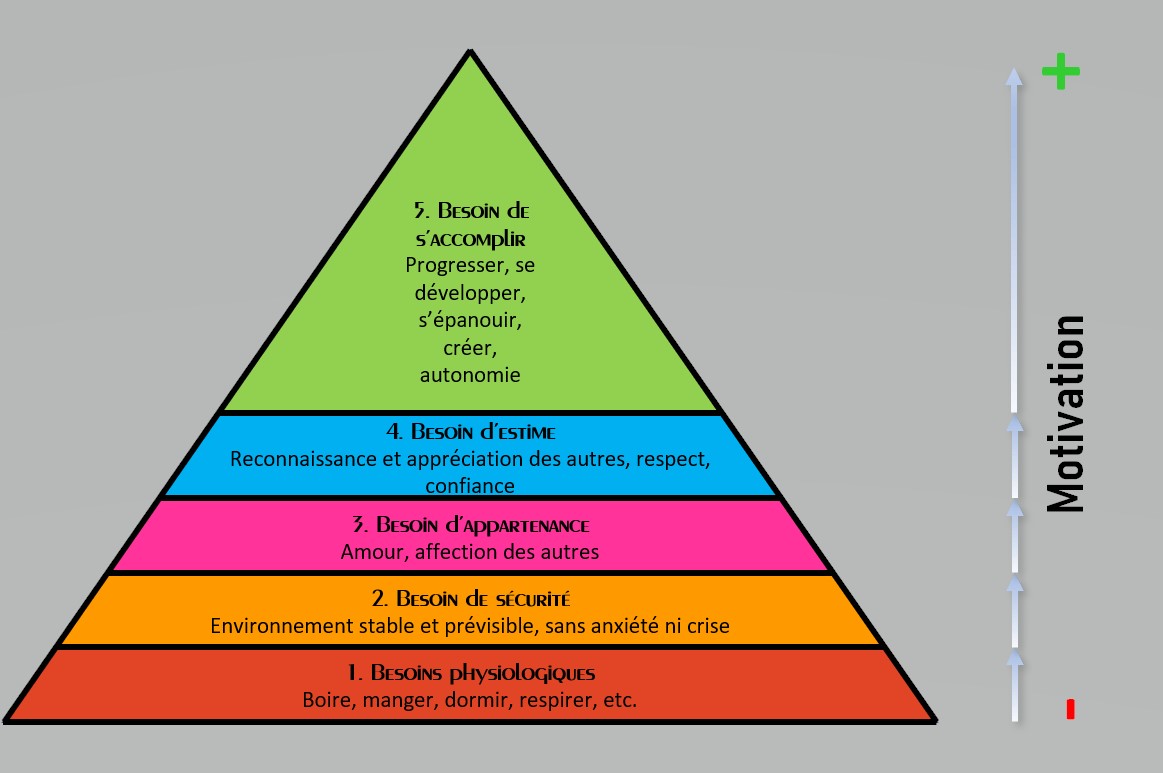

Insatisfaction Manque de motivation chronique Sentiment de ne pas s’accomplir  Sources de (dé)motivation avec ou sans nos besoins fondamentaux  Cliquez pour agrandir |

►

Le chaos cérébral décris précédemment entraine une insatisfaction

chronique et un sentiment de ne pas s’accomplir. Ils ressentent très souvent une incapacité à fonctionner à plein régime, par rapport à leurs QI ou leur capacité à comprendre rapidement les choses. – Le potentiel spécifique des adultes ayant unTrouble du Déficit de l’Attention, orienté autour de la créativité et l’intuition, est souvent mal exploité. – Ils se retrouvent dans des activités classiques demandant de la rigueur et de la régularité qui ne leur correspondent pas. – D’autant plus qu’ils peuvent passer toute leur vie à coté de leurs vrais talents, qui pourraient être mis en valeur en faisant des choix parallèles ou plus osés. – Leur manque de confiance en eux est souvent un obstacle. ► Beaucoup n’arrivent pas à poursuivre un projet de vie durable et cherchent inlassablement de nouvelles voies professionnelles et sentimentales avec un sentiment d’insatisfaction fréquent. – Certains ont quand même des périodes prolifiques du fait de cette quête de soi permanente. – Mais souvent, quand ils arrivent à l’objectif qu’ils s’étaient fixés, celui-ci leur parait bien fade par rapport à l’émotion de départ qui les avait poussés à y aller. – C’est donc souvent l’imagination ou le chemin pour arriver à l’objectif qui les motive et les concentre. – Quand ils y arrivent ils en veulent toujours plus, et ne profitent pas des gains liés à l’atteinte de leur objectif. ⇒ Certains se tirent même une balle dans le pied au moment d’atteindre leur objectif, en adoptant au fil du temps un comportement d’auto sabotage ou auto destructeur, symptôme qui caractérise plus spécifiquement le trouble borderline (trouble de la personnalité limite). ► Ce sentiment de ne pas s’accomplir et de ne subir que des échecs est lié à une stratégie de compensation qu’ils ont adopté très tôt pour ne pas accepter ce qu’ils sont et ce qu’ils font. – Ils peuvent avoir une vie normale aux yeux des autres, c’est l’interprétation qu’ils font de leur vie et des situations de vie qui est souvent déformée. – Certains font le point sur leur vie plusieurs fois par jour et ils bouclent là-dessus, au lieu d’apprécier leurs petits succès et développer ainsi un sentiment de gratitude. – Beaucoup ont le syndrome de l’imposteur même s’ils réalisent finalement ce qu’on leur demande au dernier moment. ► Il en résulte un sentiment d’insatisfaction quasi permanent surtout s’ils se sont mis en quête d’accomplissements non en phase avec leur TDAH, avec des ambitions basées sur les valeurs de la société ou de leurs parents (en phase ou en opposition), accentué par leurs pics d’optimisme trompeurs. – S’ils n’apprennent pas à observer avec du recul leur système de pensées et d’émotions (voir chapitre Solutions Intérieures), ce sentiment va les accompagner dans la deuxième partie de leur vie, avec des souffrances psychiques ou l’impossibilité d’atteindre une certaine sérénité en prenant de l’âge. ►La pyramide de Maslow ci-contre nous rappelle que nos sources de motivation qui amène à l’accomplissement permanent sont nombreuses. – On ne doit pas rester uniquement dans les niveaux bas au fur et à mesure que l’on prend de l’âge. Beaucoup d’adulte TDAH , y compris le fait de ne chercher toujours que le 4eme niveau qui est le besoin de reconnaissance, important pour nous souvent du fait de notre enfance tumultueuse. – Mais c’est le 5eme niveau qui, en harmonie avec les 4 autres , nous amènera ce sentiment d’accomplissement et donc moins de journées sans motivations ou de périodes d’insatisfaction. |

|